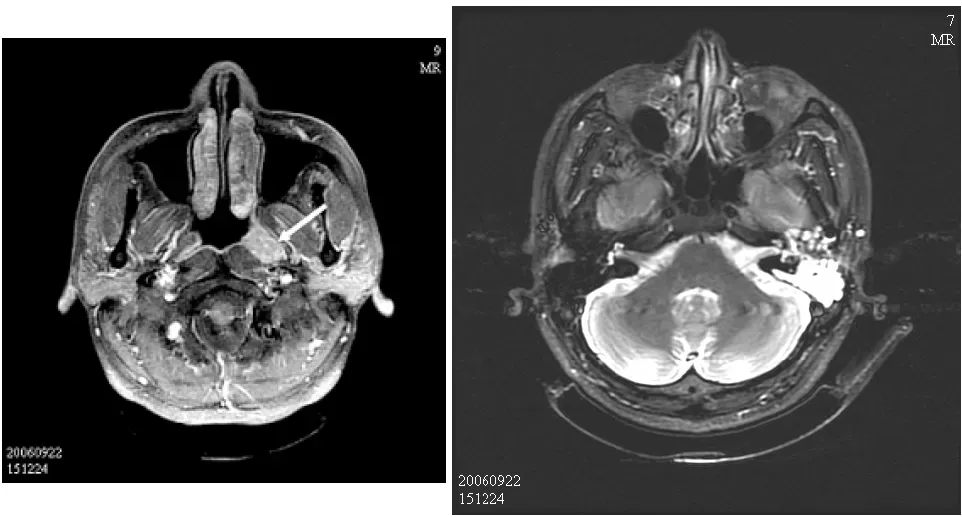

【112-1 醫學(六) 第73題】48歲男性病人主訴最近二個月左側耳鳴,根據附圖MRI之影像,箭號所指最恰當的診斷為何?

這題的解題核心在於同時辨識出鼻咽部的腫塊和乳突腔的發炎現象,並將兩者與病患的單側耳鳴症狀連結起來。圖片中箭頭指向鼻咽部的明顯腫塊,同時左側乳突腔有發炎積液的影像特徵。